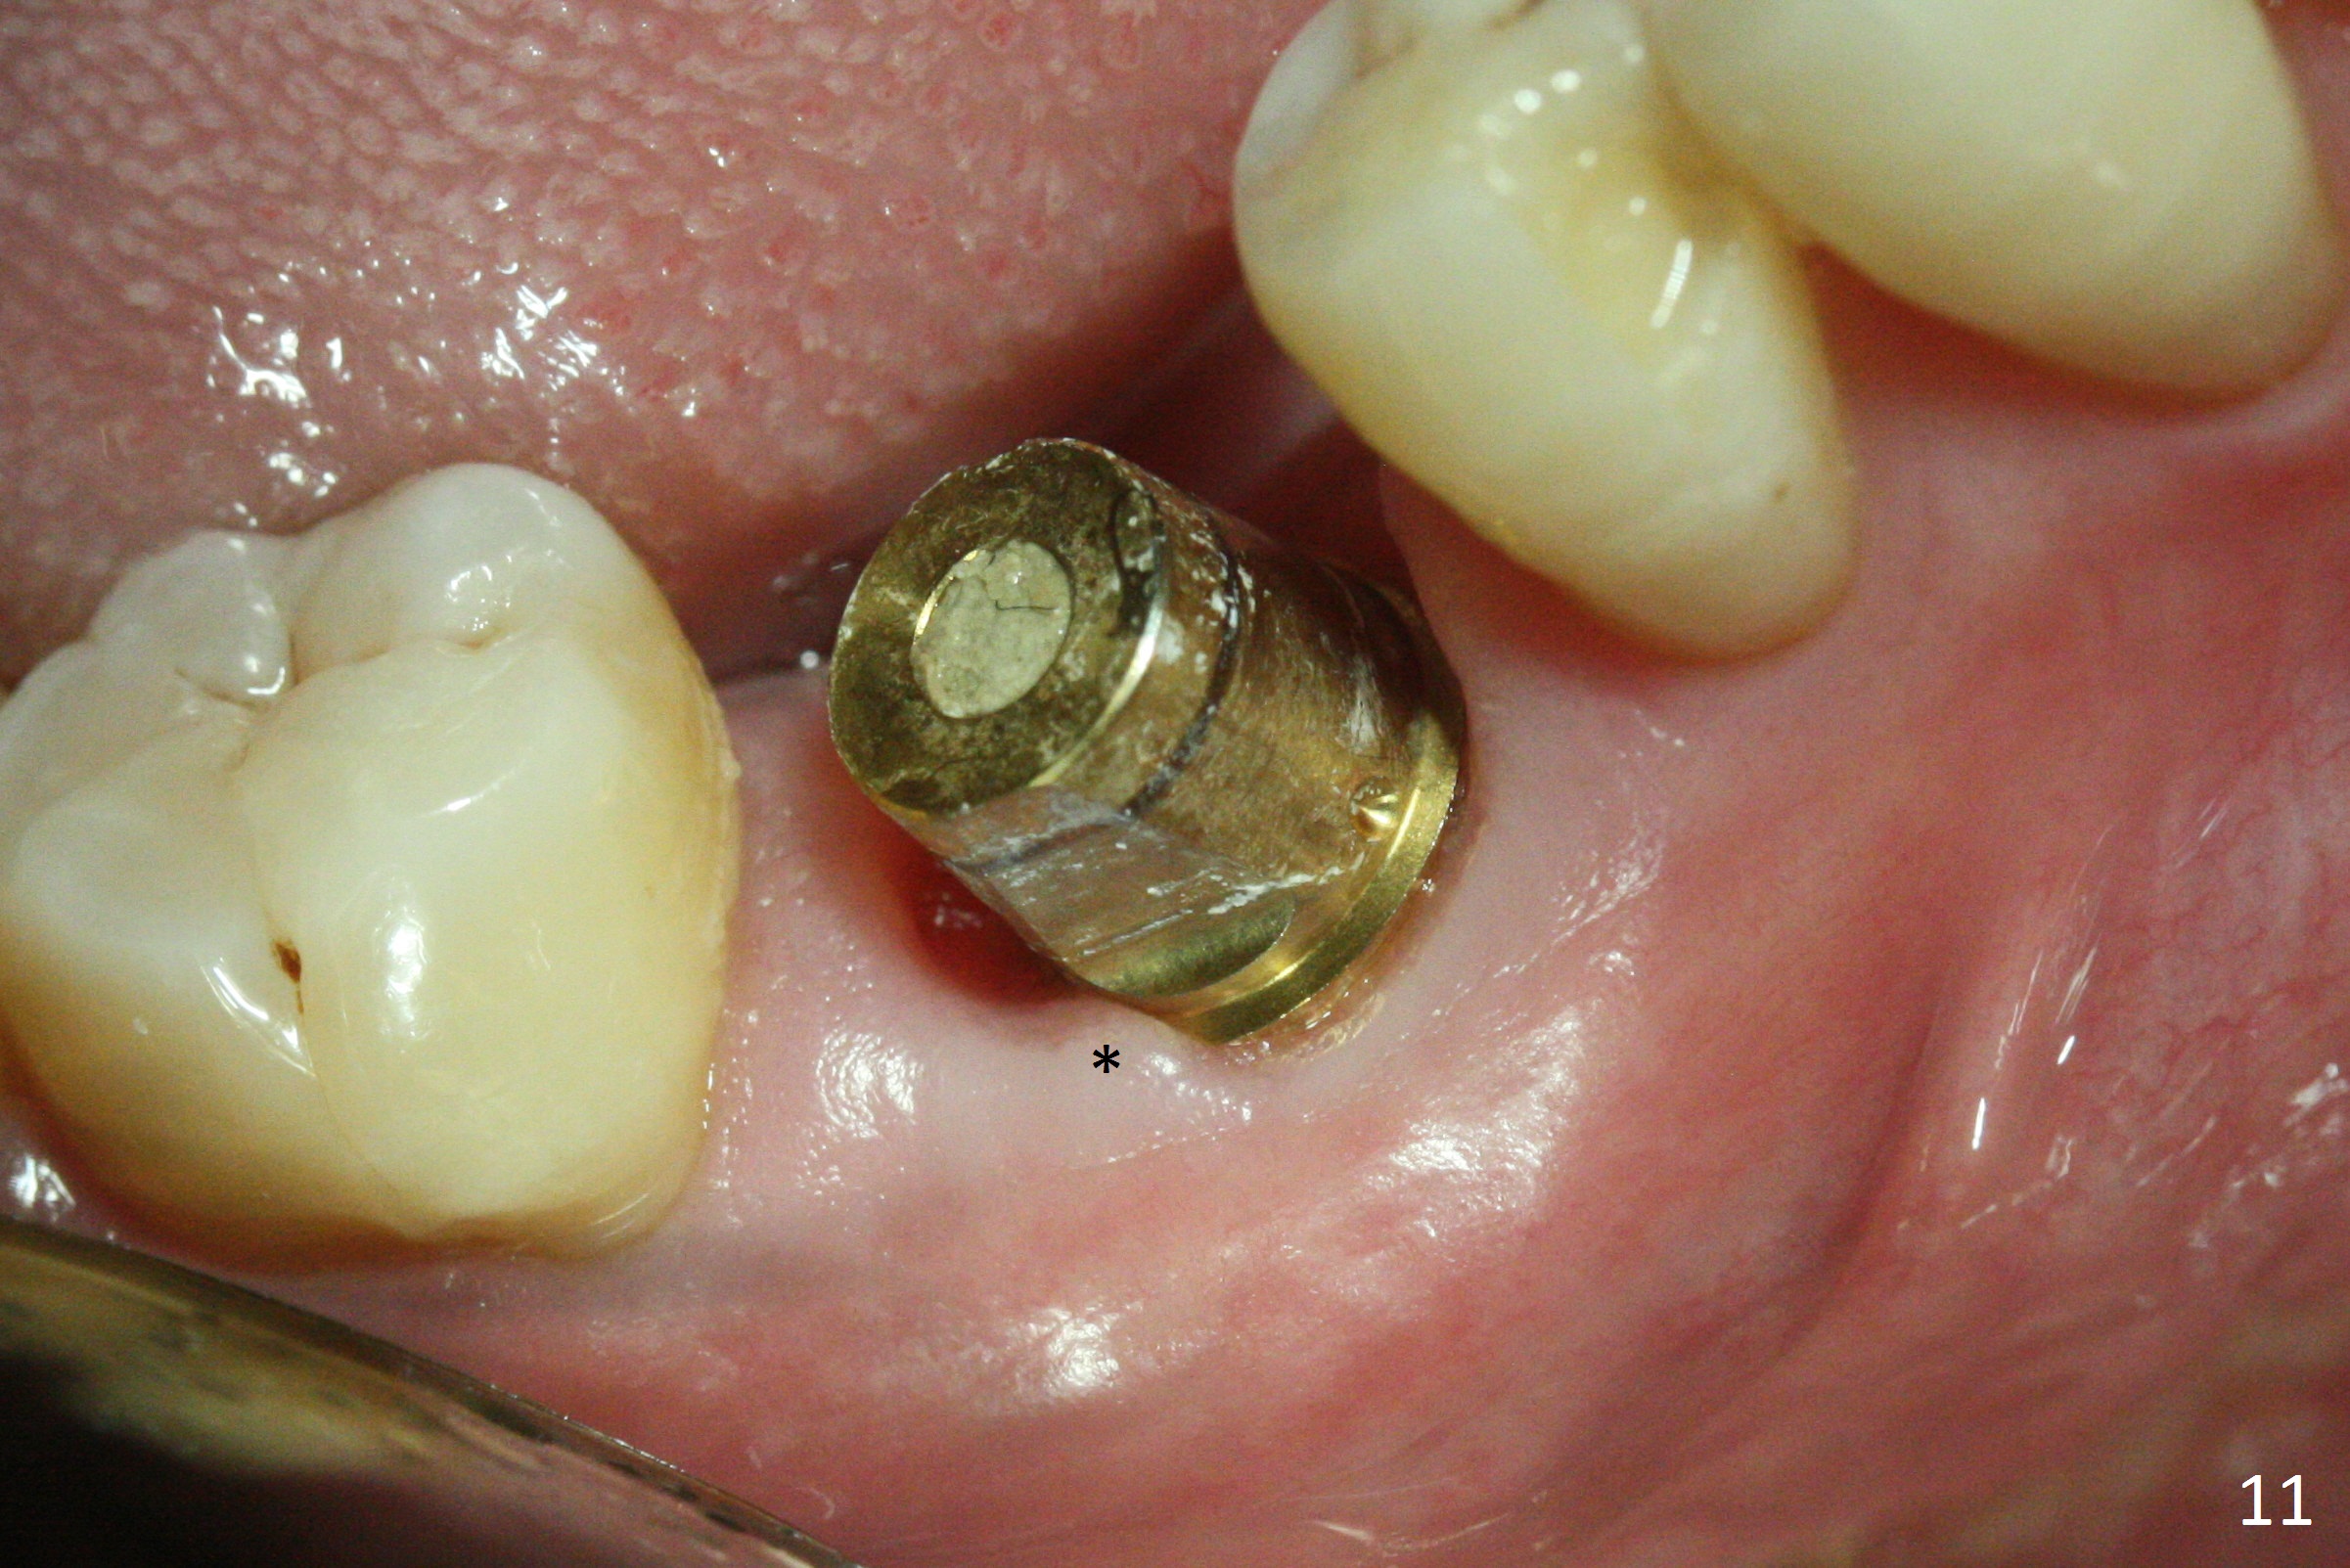

The bone (Fig.10 arrowhead) and soft tissue (Fig.11 *) heal 2 months postop. Gingivectomy is done with Diode prior to impression (Fig.12). The provisional is relined to keep the margin (Fig.13, 2 weeks later) and a permanent crown tries in (Fig.14).